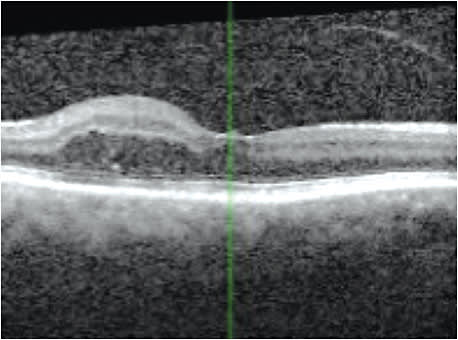

After repeated Ozurdex injections that result in improving either the VA or decreasing central macular thickness on OCT, one may want to consider longer acting, sustained-release implants, such as fluocinolone.

Patients should be closely monitored for increases in IOP, glaucoma, cataract formation and retinal detachment. The good news regarding the latter: Cutting-edge diagnostic technology, such as SD-OCT, OCTA, wide-field imaging and fundus autofluorescence, can aid us in detecting possible recurrence and, therefore, refer the patient back to the ophthalmologist for further intervention. OM